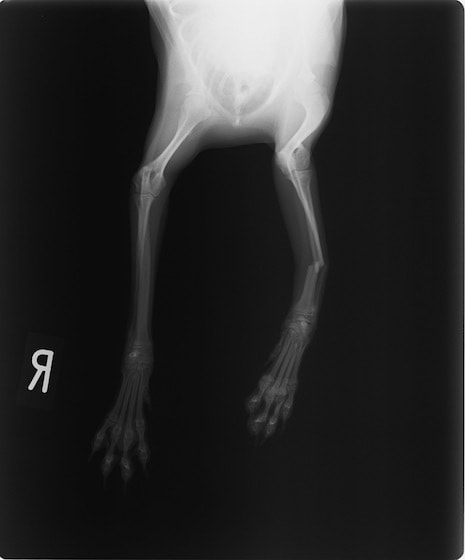

症例3:キルシュナーワイヤーのピンニングによる整復

ペルシャ猫 11ヶ月齢 雄

他院にて左大腿骨遠位の成長板骨折(salter-harrisⅠ型)が認められており、治療相談を目的として来院。当院にて、キルシュナーワイヤーを用いたピンニングにより骨折部位の整復を行いました。術後の経過は良好で、現在も経過観察中です。

術前レントゲン

術後レントゲン